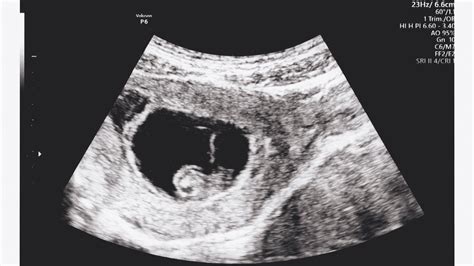

A babák testén a szőr a 12. hét körül kezd el nőni, és nagyjából a 19. hétre már az egész testükön megtalálható. A magzati szőrzet kialakulása a terhesség korai szakaszában veszi kezdetét. Az emberi test fejlődése során a természet semmit nem bíz a véletlenre, és ez a finom szőrréteg az egyik legérdekesebb védelmi mechanizmus. Ez a szőrzet a várandósság 12. hete körül kezd el megjelenni, és a 20. hétre már az egész testet beborítja.